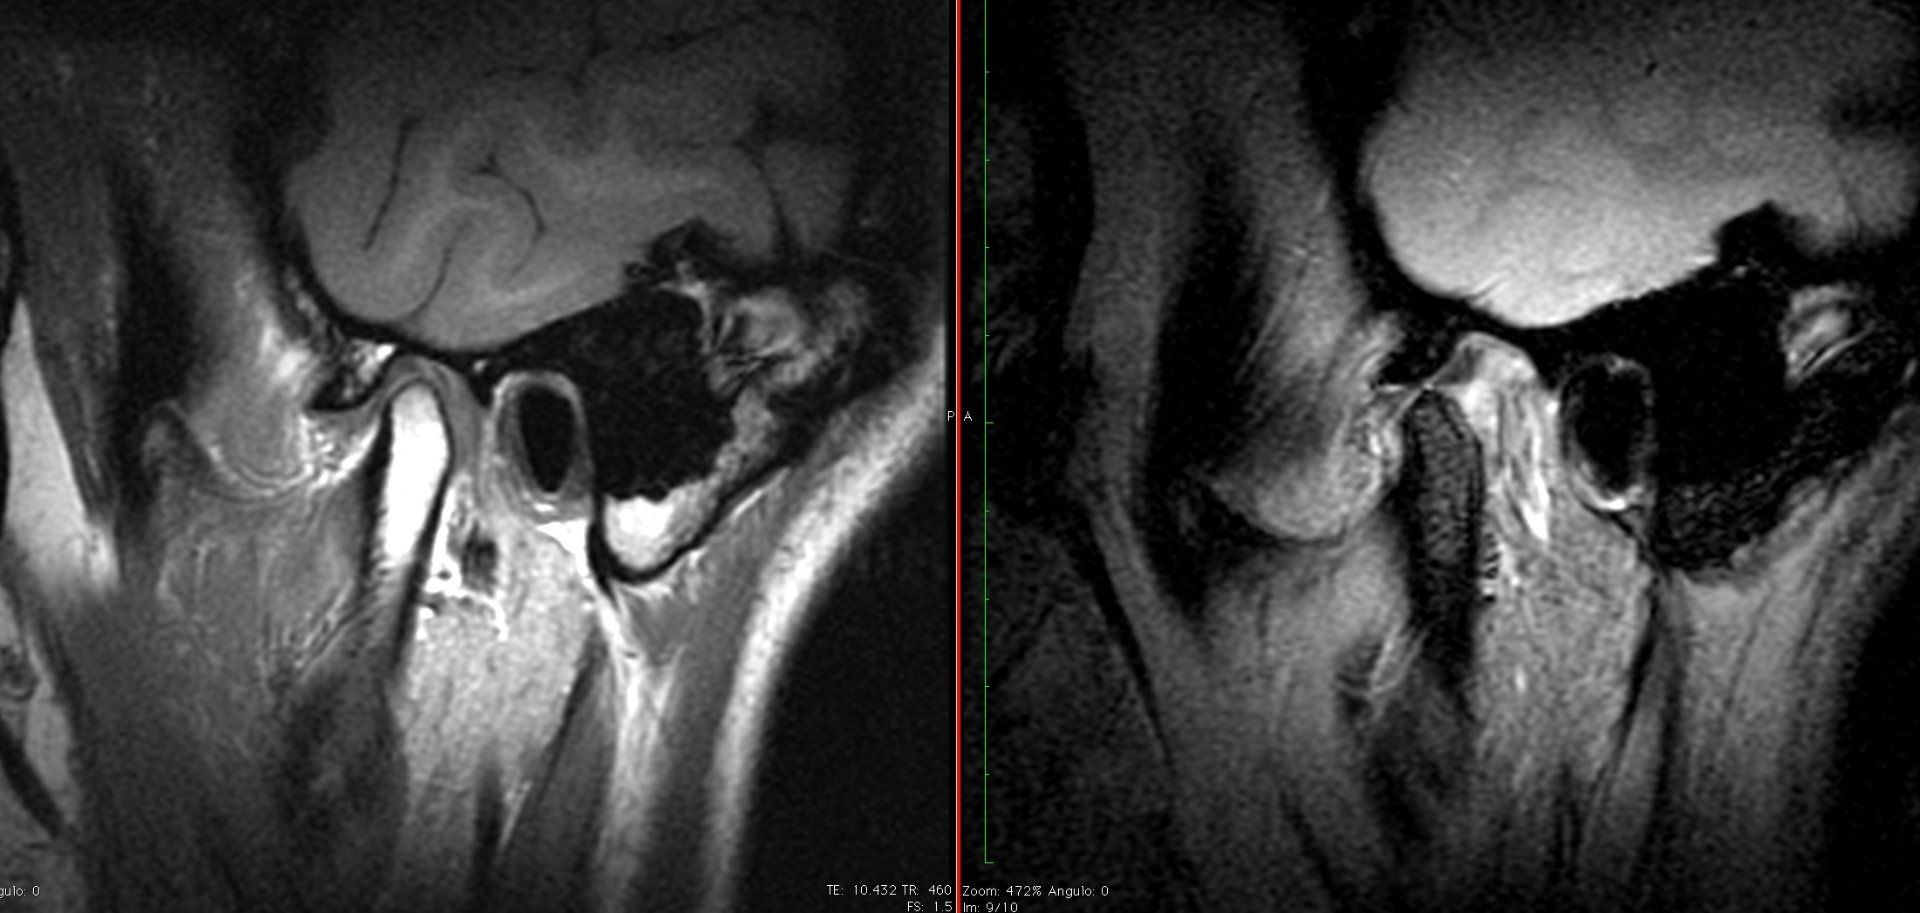

ORTOPANTOMOGRAFIAS: ( Rx Panorámica)

Son radiografías de las dos arcadas, boca completa, y ofrece una vision generalizada de todas las estructuras óseas, dentales y articulares. Estas pueden ser

frontales o

laterales.